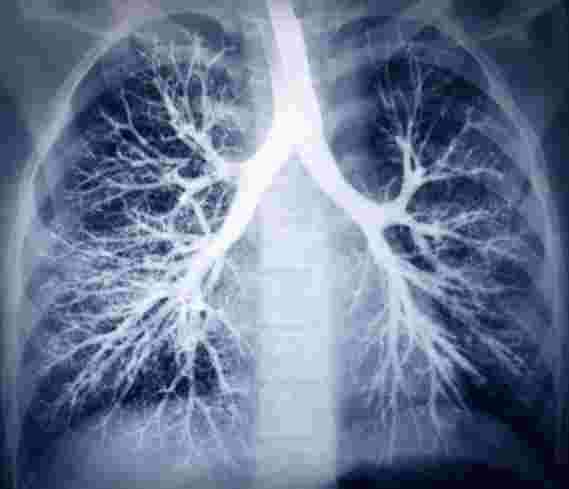

密歇根大学一项新的研究表明,与吸香烟,大麻或vape尼古丁的青少年相比,使用vape大麻的青少年患肺部疾病的呼吸道症状风险更高。

报告吸大麻的青少年比未报告吸大麻的青少年发生“喘息和吹口哨”的可能性大约高出一倍。当前使用香烟,电子烟和大麻与一些呼吸道症状(例如干咳)有关,但是在控制了吸大麻后,大多数关联并不明显。

研究人员还发现,与香烟,电子烟,使用大麻和吸大麻相比,哮喘的诊断与未来肺部损伤的症状最密切相关。

博伊德(Boyd)和费利斯(Feliz)从2016-2018年《烟草与健康人群评估研究》浪潮中的12-17岁青少年样本中研究了自我报告的症状。症状是:胸部喘息和吹口哨;喘息引起的睡眠障碍或语言受限;在运动中或运动后听起来有些喘息;夜间干咳与胸部疾病或感染无关。